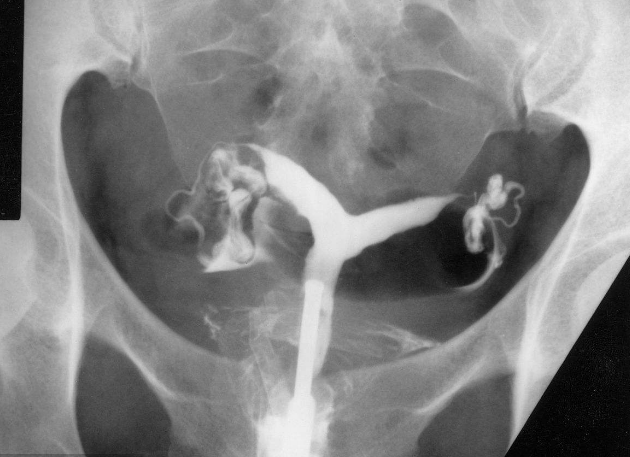

子宮輸卵管造影

雙角子宮圖片

雙角子宮 (8)